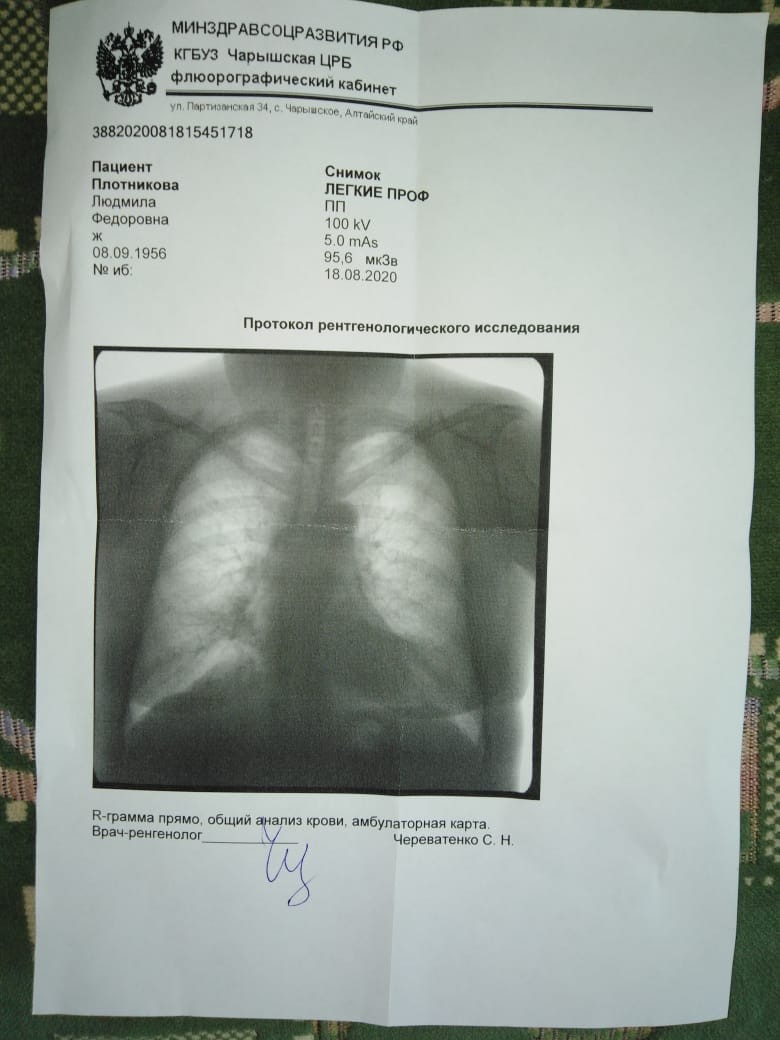

Фотографии рентгеновских снимков без необходимости направления от врача